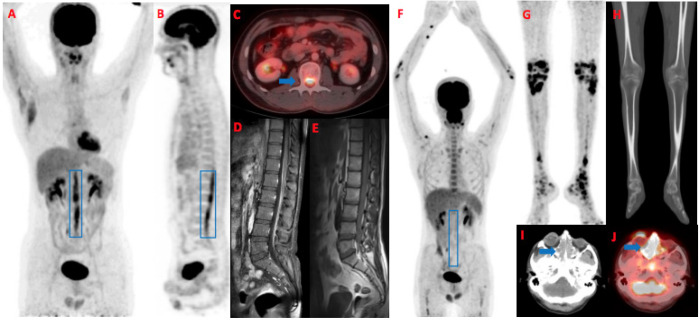

Neurolymphomatosis (NL) is a rare clinical condition characterized by the infiltration of malignant lymphocytes into the cranial or peripheral nerves, nerve roots, or plexus. Diagnosis can be clinically challenging due to its variable presentation. It usually occurs in B cell lymphoma; however, a few cases of extranodal killer/T cell lymphoma. Most cases present at a secondary site in patients with primary site in remission. 18Fluorine fluorodeoxyglucose positron emission tomography/computed tomography plays an important role in the early detection of NL, resulting in timely treatment. We present a case of a 24-year-old male with nasal natural killer T cell lymphoma who initially responded to treatment but relapsed with NL based on clinical and radiological findings.